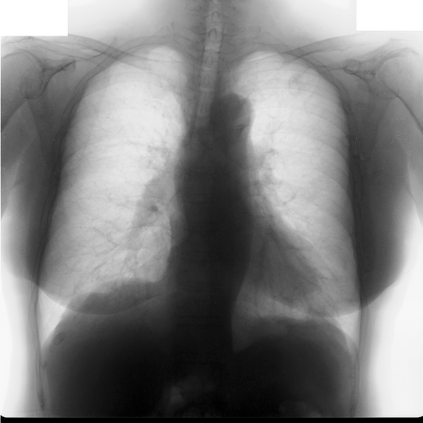

Multi-organ segmentation of X-ray images is of fundamental importance for computer aided diagnosis systems. However, the most advanced semantic segmentation methods rely on deep learning and require a huge amount of labeled images, which are rarely available due to both the high cost of human resources and the time required for labeling. In this paper, we present a novel multi-stage generation algorithm based on Generative Adversarial Networks (GANs) that can produce synthetic images along with their semantic labels and can be used for data augmentation. The main feature of the method is that, unlike other approaches, generation occurs in several stages, which simplifies the procedure and allows it to be used on very small datasets. The method has been evaluated on the segmentation of chest radiographic images, showing promising results. The multistage approach achieves state-of-the-art and, when very few images are used to train the GANs, outperforms the corresponding single-stage approach.